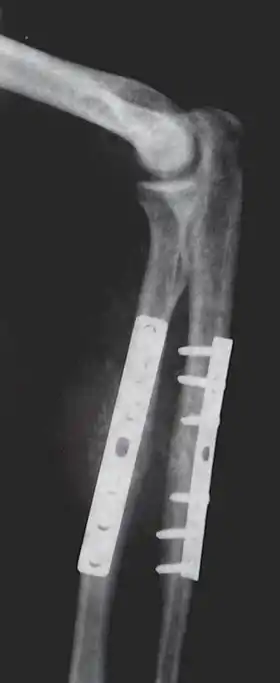

Orthopedic

Orthopaedic implants help alleviate issues with the bones and joints of the body.[7] They are used to treat bone fractures, osteoarthritis, scoliosis, spinal stenosis, and chronic pain. Examples include a wide variety of pins, rods, screws, and plates used to anchor fractured bones while they heal.[3][5][6]